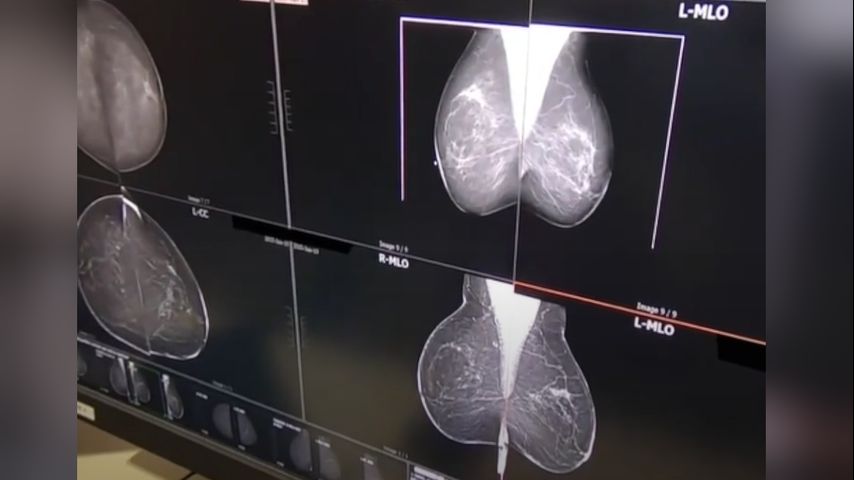

Wednesday's Health Report: Inside new innovations in breast cancer surgery

BATON ROUGE — About 2.3 million women are diagnosed with breast cancer annually.

Treatment for breast cancer may include personalized therapies or surgery.

A lumpectomy removes the cancerous tissue and margin areas, while a mastectomy removes the entire breast.

Dr. McLaughlin explains that decades of research have shown similar long-term survival rates for both operations.

Surgical innovations are improving care and quality of life. Some patients no longer need lymph nodes under the armpit removed, and techniques remove less skim while preserving the nipple and areola complex.